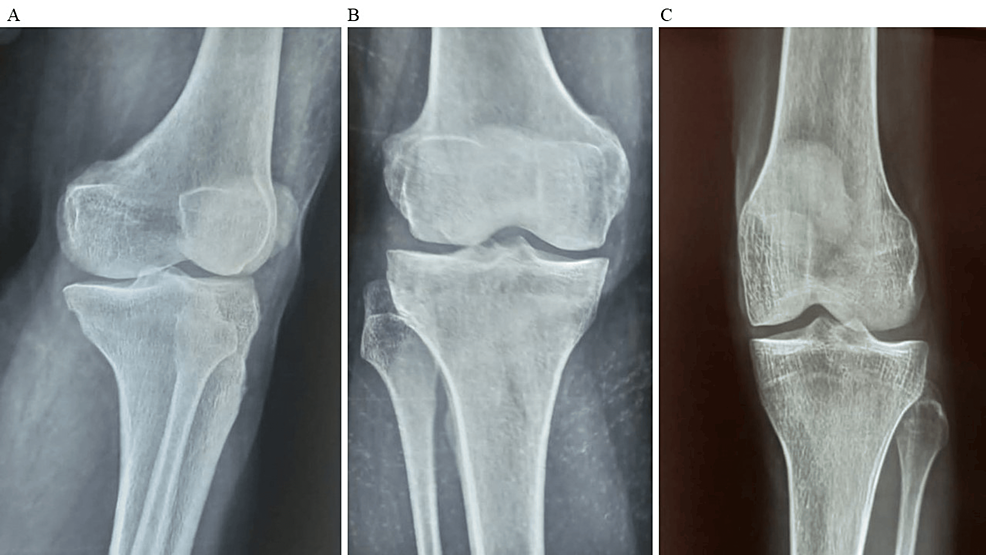

除了骨關(guān)節炎外,15名參與者還被發(fā)現患有骨缺損,占該隊列的30%。這些缺損包括各種情況,例如骨折、退行性骨病或先天性畸形,突顯了研究中涉及的骨科問(wèn)題多種多樣。下圖1顯示了開(kāi)始干細胞治療之前的骨骼側視圖和前后視圖。

圖1:顯示了開(kāi)始干細胞治療之前的骨骼側視圖和前后視圖。

圖1:A:干細胞治療前(側視圖),B:干細胞治療前前后位(AP)視圖,C:干細胞治療前前后位(AP)視圖。